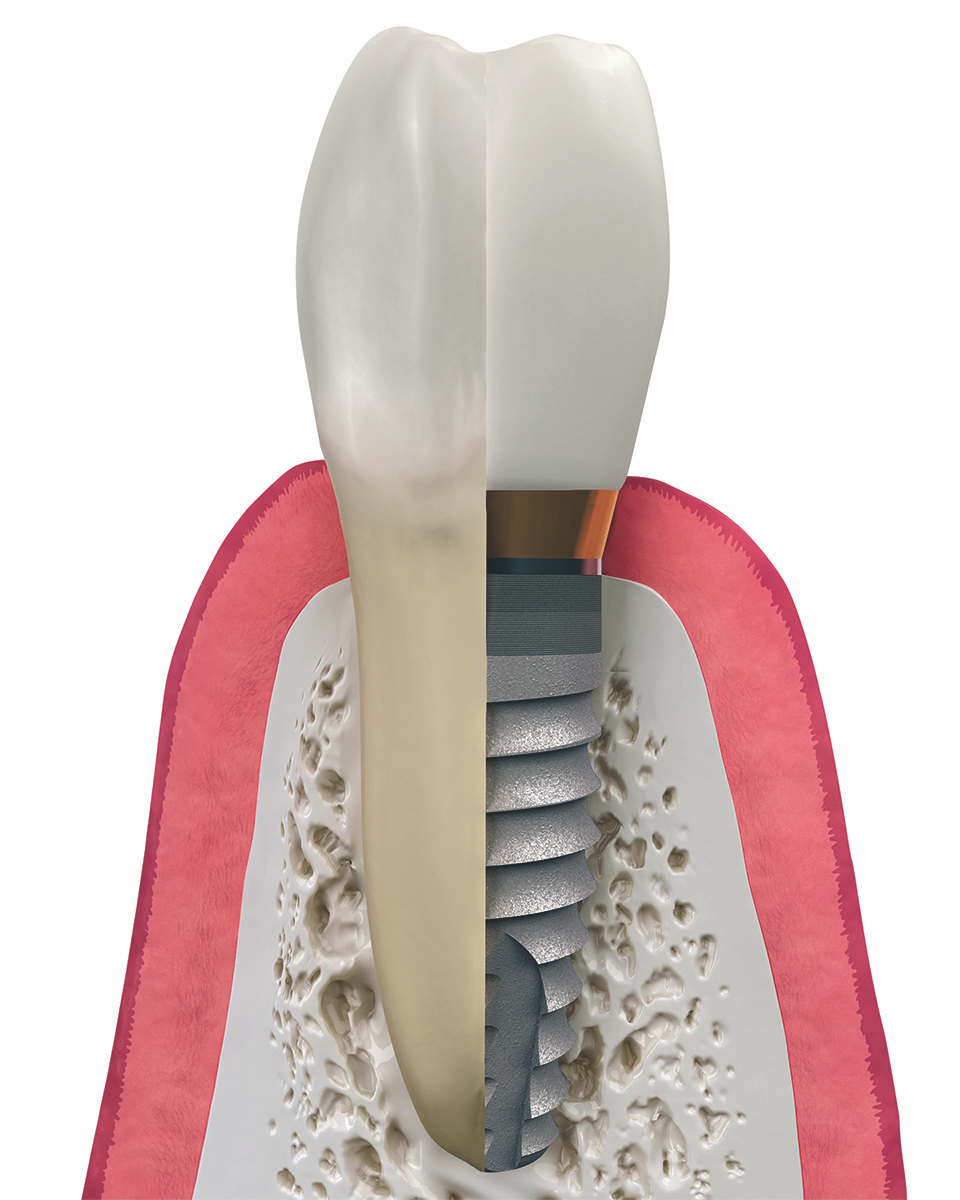

Step 4: Dental Implant Placement

Once the bone is ready, the titanium implant post is placed into the jawbone. This step is done with local anesthesia and advanced guidance technology for accuracy. Many of our patients prefer oral sedation to be even more comfortable!

The implant acts as the “root” of your new tooth.

Most patients experience only mild soreness, usually less than having a tooth extracted.

Step 5: Healing & Osseointegration

After placement, the implant undergoes a natural healing process called osseointegration. This means the bone fuses to the implant surface, creating unmatched stability.

Healing typically takes 3–4 months, though timelines vary.

Once healing is complete, we attach the custom abutment and crown.

The crown is designed to perfectly match the shape and color of your natural teeth.

Our high-quality ceramic materials are both durable and lifelike.

The result: a tooth that looks, feels, and functions just like your own.